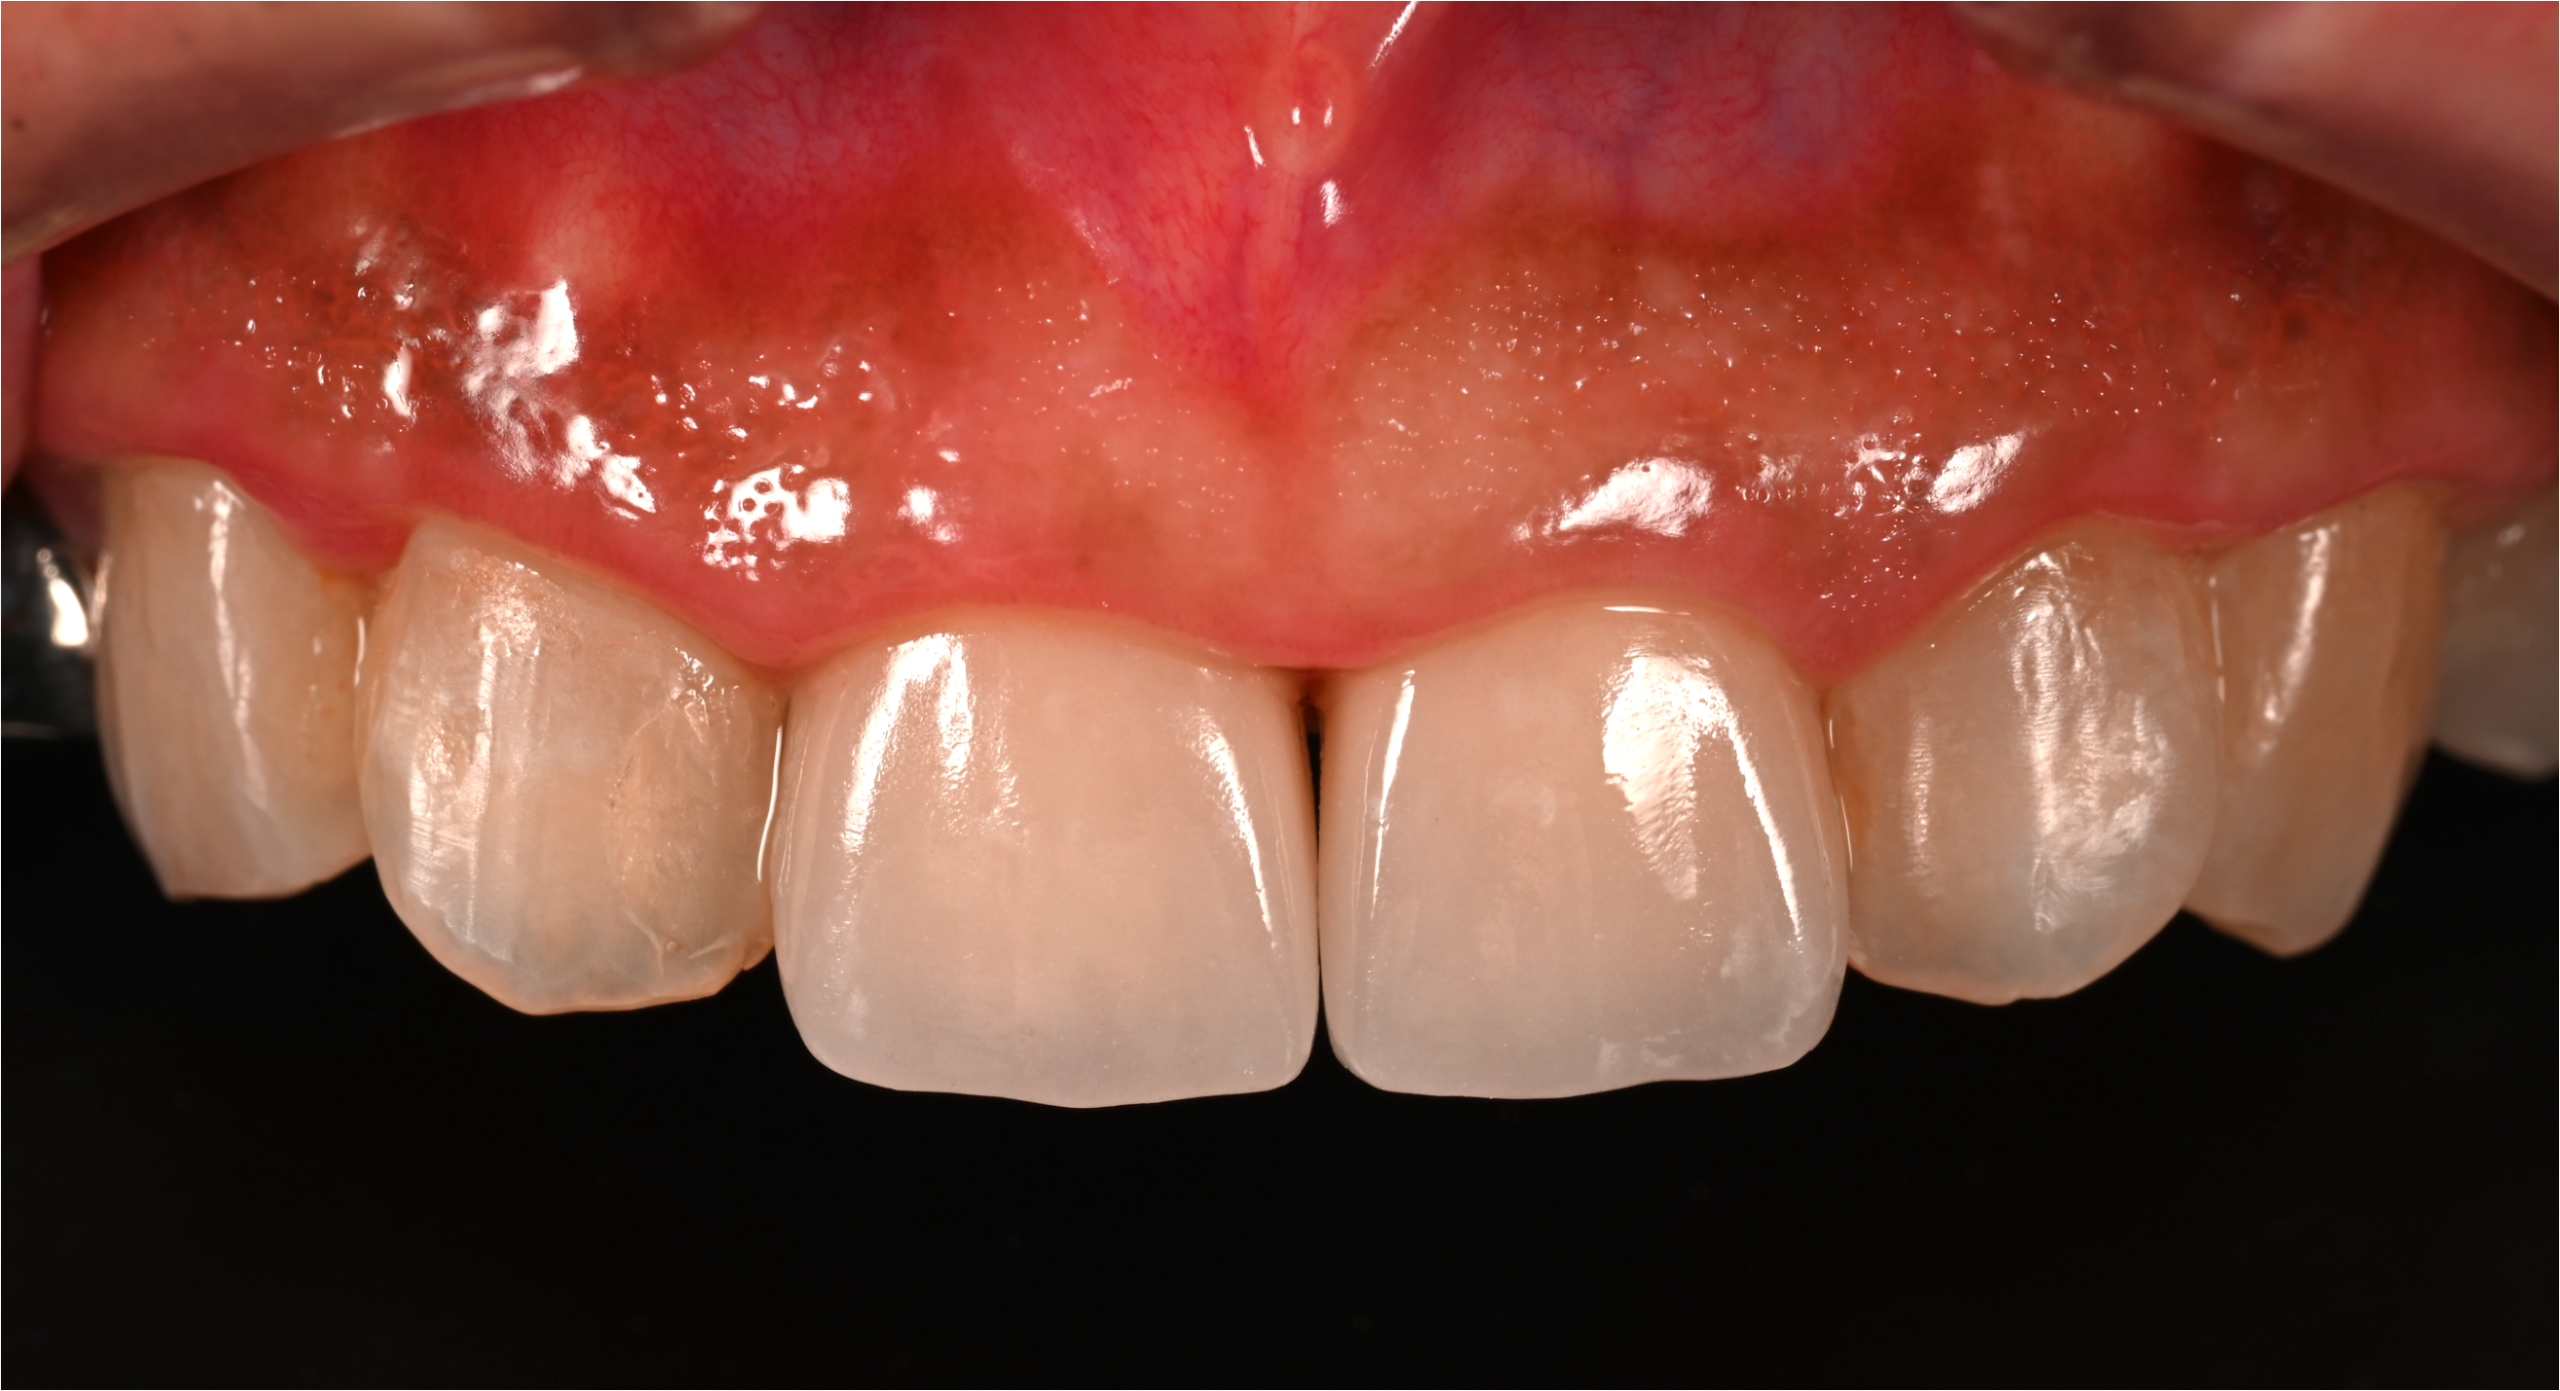

治療後

| 治療内容 | 虫歯治療、セラミックブリッジ治療 |